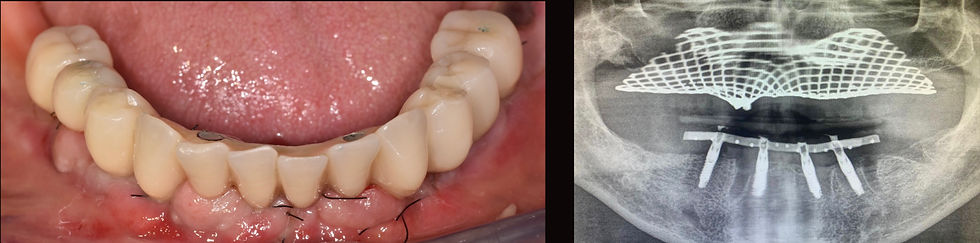

Provisional prosthesis at delivery and x-ray check

4 months post-operative impression

Relationship between the lower Toronto Bridge and the neck of Prama Long Neck implants